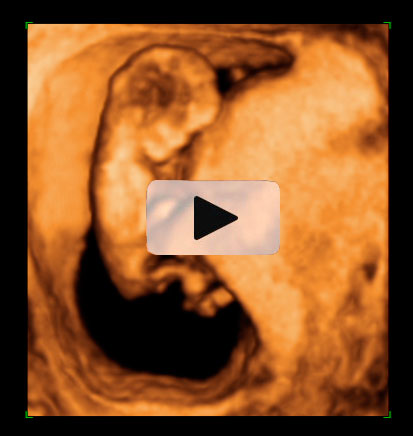

La ecografía permite medir a este feto de 12 semanas. Con esta medición se comprueba cómo crece a lo largo de las semanas. Para ello se toma la distancia que existe entre la coronilla y el final de la columna vertebral.

Embrión con una longitud de 57 milimetros,

Desde la cabeza a la rabadilla, la llamada longitud cráneo-caudal (CRL). Corresponde a 12,1 semanas de gestación.